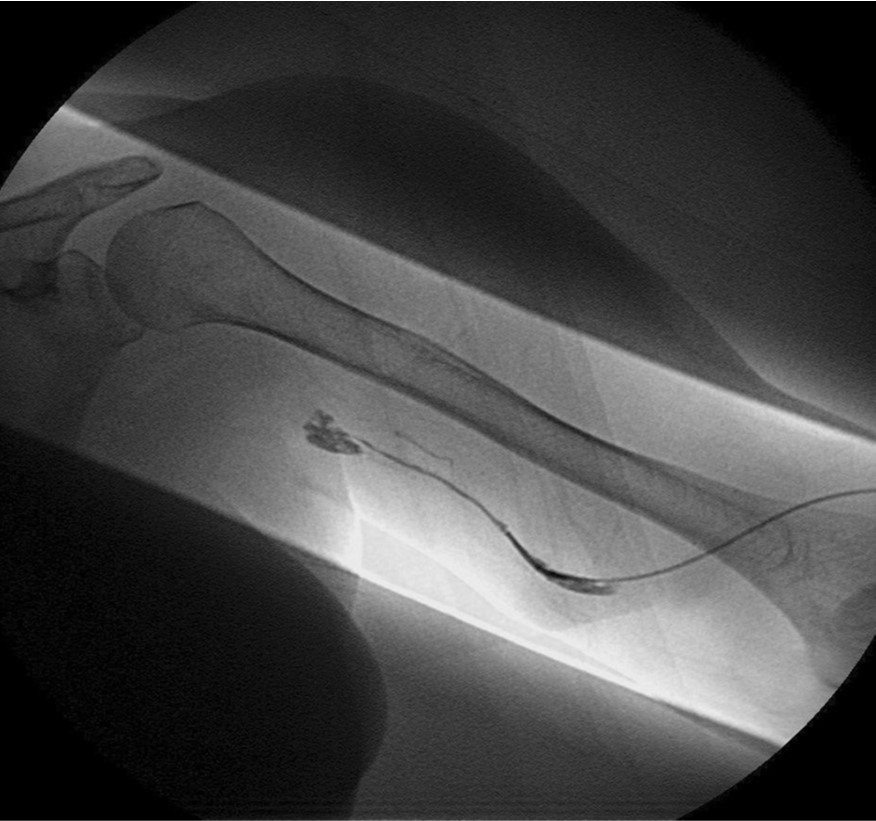

환자의 AV fistula는 초음파상 total thrombotic occlusion 된 상태였으며 시술 전 urokinase 100000 unit를 사용하여 thrombolysis and aspirated thrombectomy를 시행하였다. 그 후 시행한 shuntogram(Fig. 1) 상 left basilic vein 의 total ocdusion을 보이며 초음파상 remant vein의 크기는 1mm 이하로 확인되었다. 투시하에서 확인되는 outflow vein은 없었기에 초음파 유도하에 5 Fr Kumpe catheter(Soft-Vu, AngioDynamics, USA, NY) 에 0.035’ straight-tip guide wire(Terumo, Tokyo, Japan)를 사용하여 막힌 left basilic vein으로 15cm 이상 진행하였으며(Fig. 3), 4mm balloon (synergy, Boston, Ireland)를 사용하여 blind angioplasty를 하며 true lumen으로의 진행을 시도하였으나 실패하였다(Fig. 4). 더 이상의 antegrade로의 접근은 어려울 것으로 판단하여 regrograde approach를 위하여 left internal jugular vein 을 초음파 유도하에 9Fr sheath( Accu-Sheath, Sungwonmedical, Korea, Cheongju)을 사용하여 access 하였다. (Fig. 5A) 그리고 5Fr Cobra & sherpherd hook catheter (A&A M.D., Korea, Sungnam) 를 이용하여 left axillary vein으로의 접근을 시도하였다(Fig. 5B).

Fig. 3.

A-B. Guide wire negotiation into occluded left basilic vein with 4mm balloon